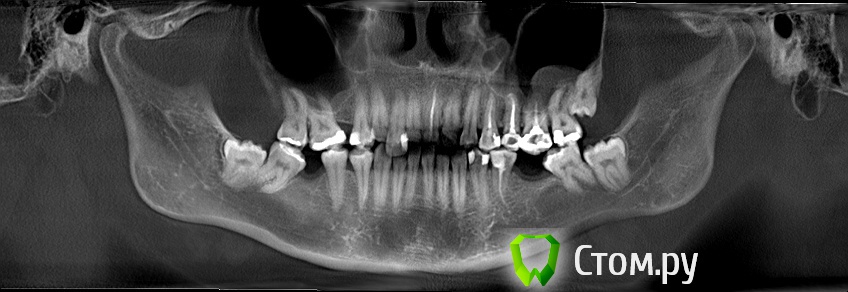

melania Опубликовано 13 мая, 2014 Поделиться Опубликовано 13 мая, 2014 зуб 15 лет назад депульпированный. пломба составляла большую часть зуба. со временем разрушилась, осталась одна стенка и то искусственного материала. сейчас при посещении стоматолога слышу что зуб резецированный (?) . никаких операций не было. сам корень синий (вижу через десну просвечивает.\ принято решение перепломбировать каналы и поставить вкладку +коронку. вопросы собственно -1. насколько это актуально, не разрушится ли все в ближайшее время.2. планируются брекеты (проблемная сторона противоположная.) ортодонт считает что этот зуб не помешает ситуации. и на него брекет ставить не будет. не вызовет ли подвижность соседних зубов при перемещении проблем? на фото зуб до перепломбировки канала. на сегодняшний день уже запломбировали заново, потому что в верхушке канала просматривалась пустота. Ссылка на комментарий

Гарриевич Опубликовано 14 мая, 2014 Поделиться Опубликовано 14 мая, 2014 скорее всего "резорциненый" собственно о каком зубе речь?Выкладывайте снимки после лечения. О 25.По мне так нормально пролечен, по этим снимкам Ссылка на комментарий